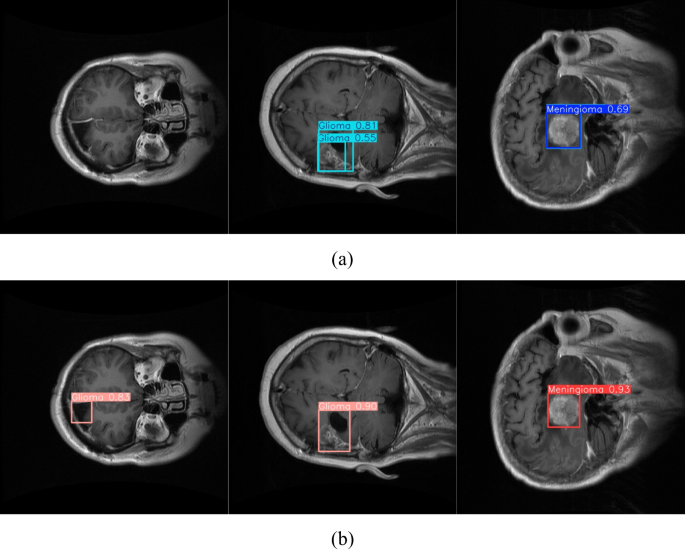

As illustrated in Fig. 9, notable differences can be observed between the detection results obtained by YOLOv12n and the proposed method on brain MRI images. For Glioma, YOLOv12n exhibited issues such as duplicate bounding boxes and relatively low confidence scores (0.81 and 0.55). In the case of Meningioma, the confidence score was only 0.69, reflecting instability in lesion boundary localization. In contrast, the proposed method produced more precise and concise detection outcomes, successfully eliminating duplicate bounding boxes and substantially improving confidence scores: 0.83 and 0.90 for Glioma, and 0.93 for Meningioma. Overall, the proposed approach surpasses YOLOv12n in localization accuracy, confidence, and result consistency, clearly demonstrating its advantages and reliability for medical image detection tasks.